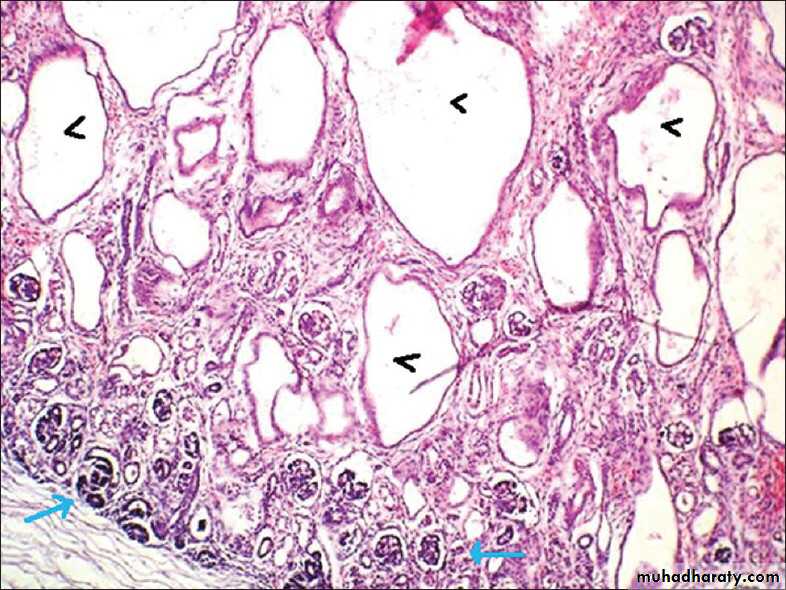

This sporadic disorder is due to an abnormality in metanephric differentiation,.

Characterized histologically by the persistence in the kidney of abnormal structures, cartilage, undifferentiated mesenchyme and immature collecting ductules and by abnormal lobar organization.Most cases are associated with ureteropelvic obstruction, ureteral agenesis or atresia and other anomalies of the lower urinary tract.

Dysplasia can be unilateral or bilateral and is almost always cystic.

Cystic Renal Dysplasia